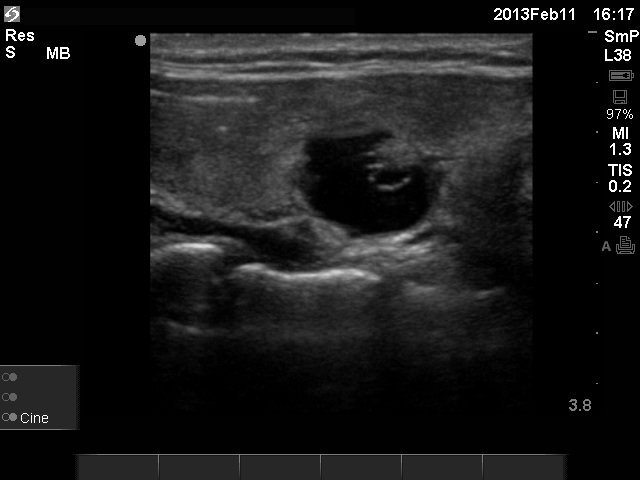

Follow-up - 27 months after initial investigation (ultrasonographic picture 3)

Right lobe, longitudinal scan. There are minimally hypoechogenic areas ventral to the cystic nodule.